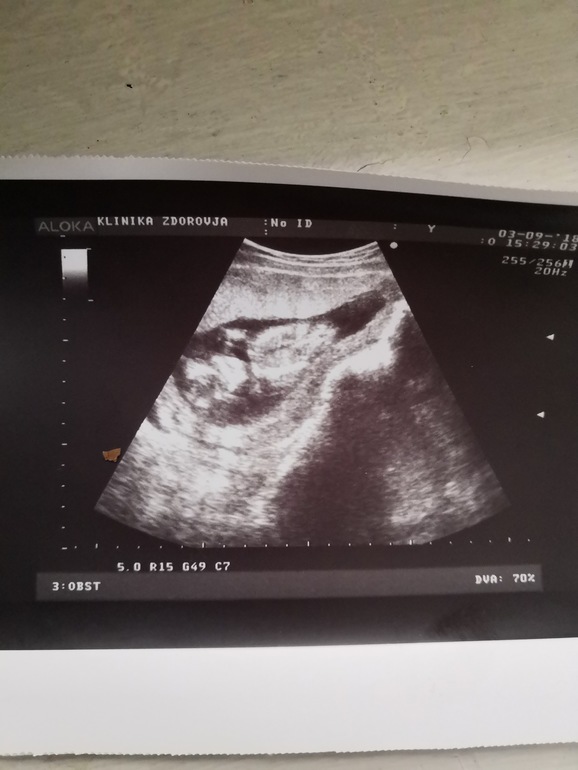

это со скрининга,уж совсем не понятная для меня фотка,как попало сфоткали и отдали, очень не нравится эта узистка мне с жк,

Пол тогда тоже не сказала, вообще не видно сказала (хоть особой разницы небыло,но было интересно), недели через две я решила повторить узи,и пол уточнить и про шейку разузнать. Шейка такая же была ну 30-32 сказала узистка,и тонус был,пол сразу увидели